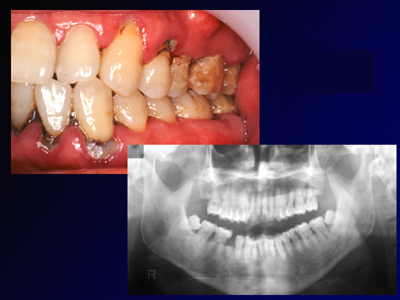

浮腫性の歯肉、全顎にわたりpd8〜10mm、著しい動揺がみられる重症例です。

(下顎前歯部歯肉に注目ください)

1ヶ月後、プロービングデプスは2〜3mmに改善しました。